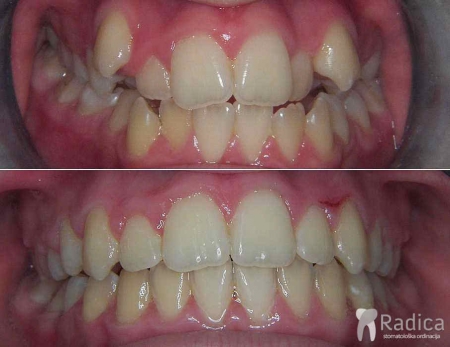

Kompresija –fiksni aparat, bez ekstrakcije:

Kompresija –fiksni aparat, vađenje četri premolara – po dva u svakoj čeljusti: